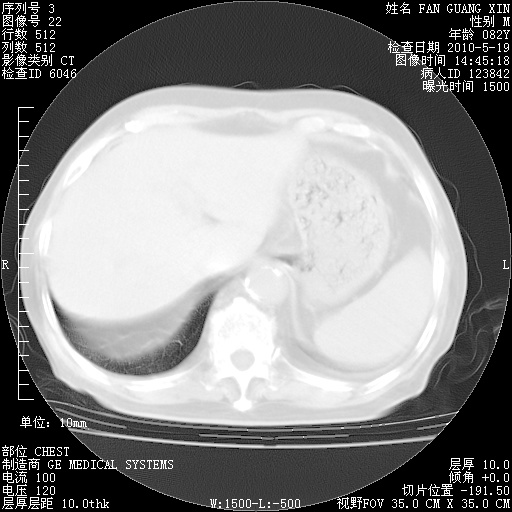

复查肺部CT,明显好转。为什么发热呢?

治疗3周后的肺部CT

治疗3周后的肺部CT纵隔窗